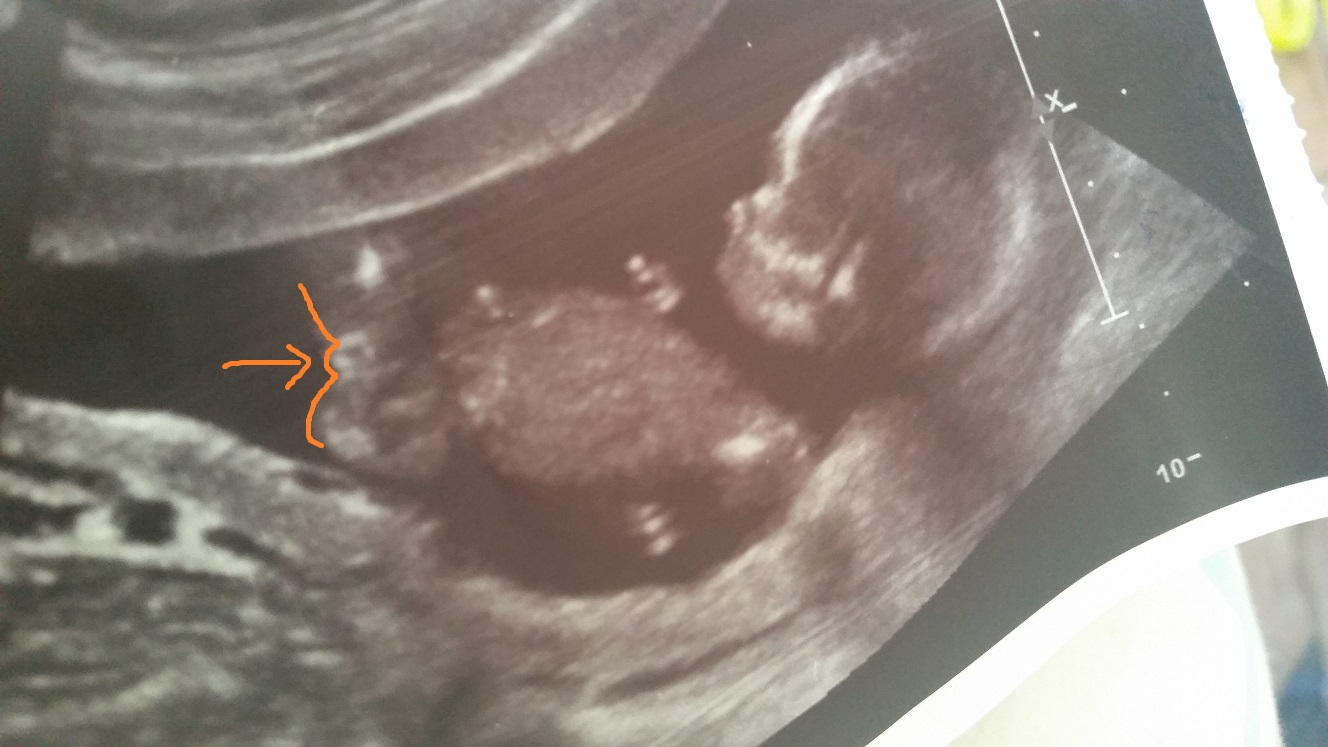

This is my 15 weeks 2 day ultrasound, the tec said it wasn't ovious yet what gender the baby is but I keep seeing what looks like two lines and a dot between the legs?

The only semi decent pic I have that would give me some idea is this one unfortunatly, Im not sure but I think that what iv put the arrow to may be its bits but not sure.

I have two boys already and I have to say im terrible at making out these images, I could never see any boy bits with either of them even at 20 weeks!